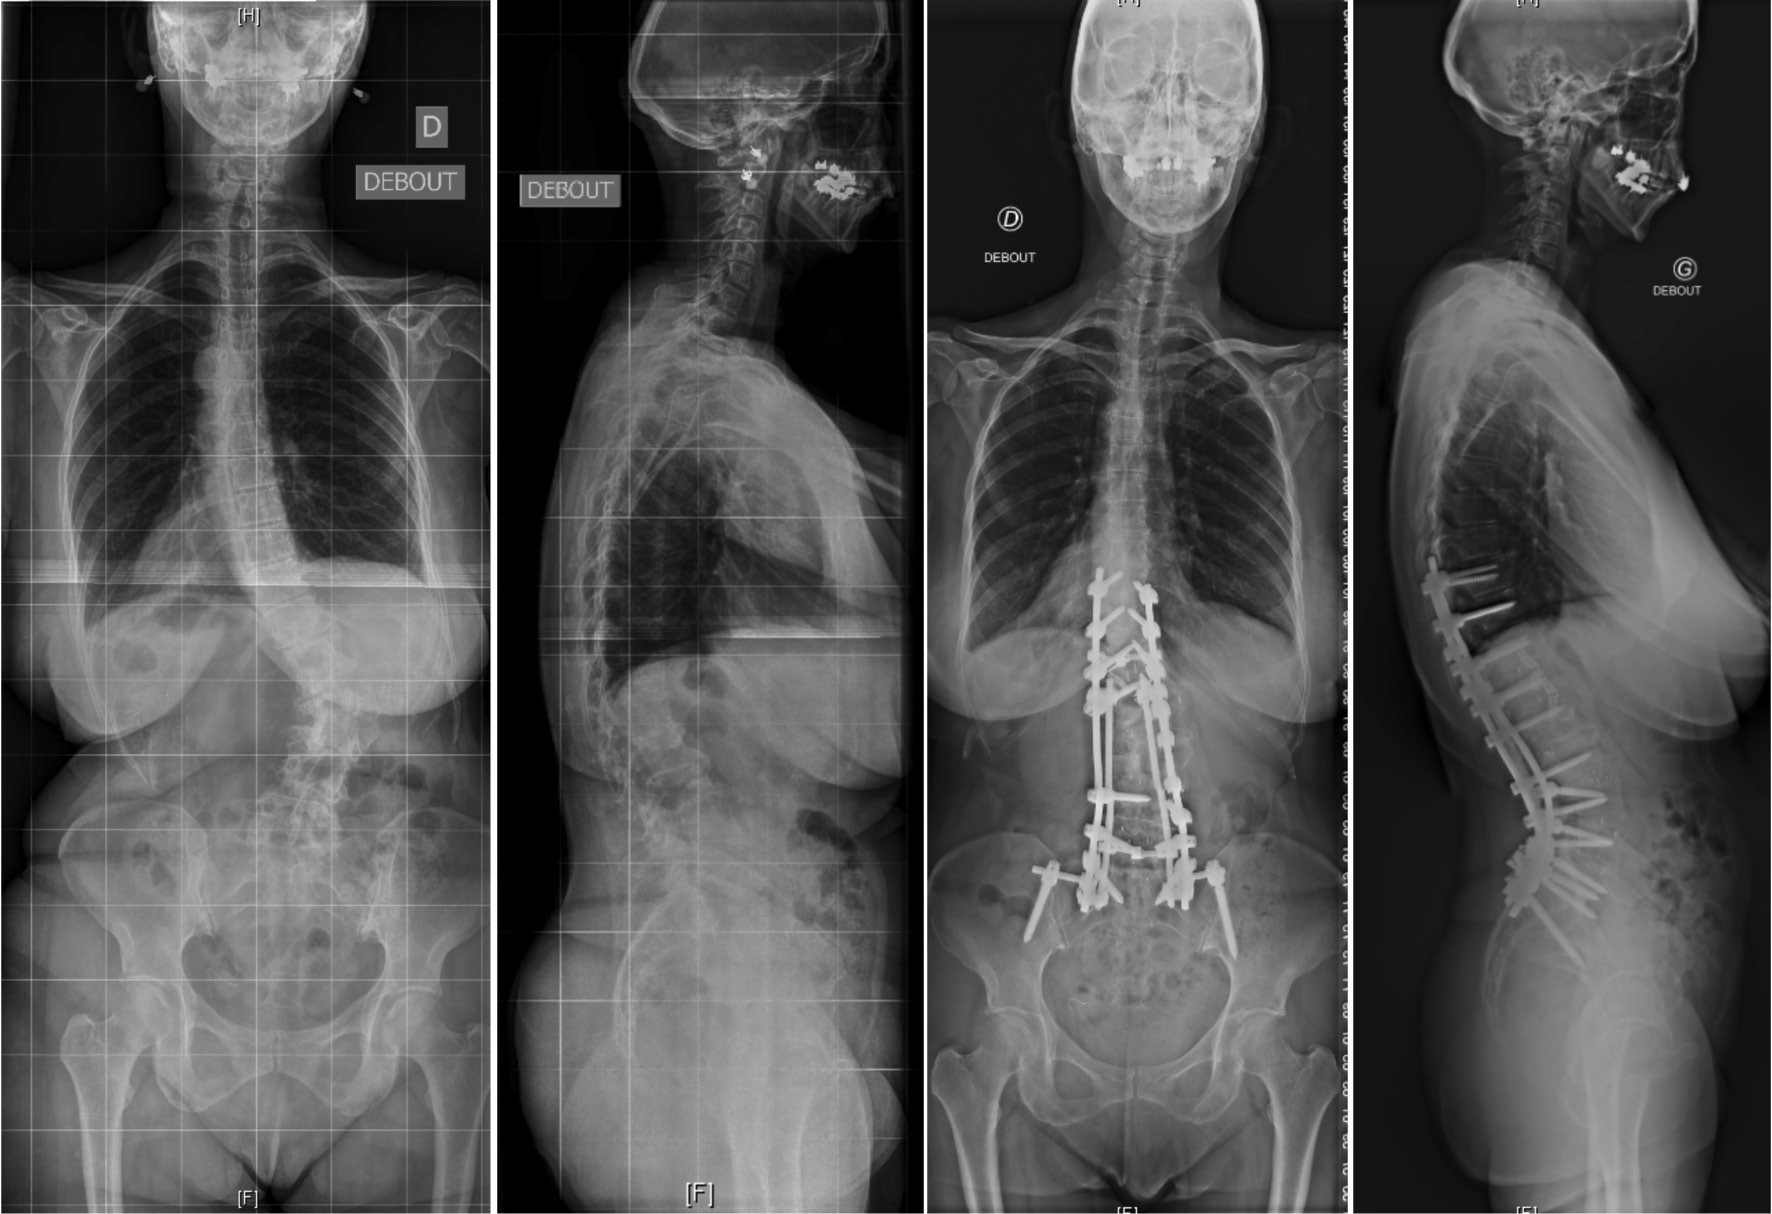

脊柱形态与症状来源

成人脊柱侧凸通常与腰椎前凸的丢失与胸腰交界处的后凸畸形有关,从而导致躯干前倾造成失平衡,此时人体往往会通过骨盆的后倾和膝关节的屈曲进行代偿。不断进展矢状面畸形最终会影响患者的健康相关的生活质量(HRQoL)。同时,由于椎旁肌的能量消耗增加以抵消身体前倾所造成的失平衡,从而导致腰背痛,肌肉劳损和活动功能障碍。

成人脊柱侧凸畸形与后凸畸形

微创治疗占据一席之地

在过去的十年中,微创MIS技术治疗ASD已取得了重大进展。微创手术方式通常是通过前路腹膜后入路椎间融合器植入与后路经皮内固定相结合实现手术减压、固定及融合的目标。这种手术方式更适用于轻度到中度的ASD患者,此类患者多表现为有限节段的腰椎退行性改变和较好的弯曲柔韧性。对于MIS手术,单或双节段的退变为MIS治疗的良好手术指征,此时进行早期干预能够防止弯曲进一步的发展。目前已存在较多的文献表明通过MIS技术能够有效地矫正腰椎畸形,并且可以改善腰背痛以及神经根性疼痛。 Phan等对MIS技术治疗ASD患者进行荟萃分析后提出MIS技术的远期融合率满意且并发症发生率相对较低。Kanter等在其对MIS技术治疗ADS患者的综述中表明MIS技术在带来满意疗效的同时能够降低围手术期并发症。但是因其矫形能力有限,不建议将其应用于严重畸形的病例。

MIS技术通过结合后路经皮内固定和侧前路椎间融合器,使椎体获得重新排列,并对椎间孔狭窄进行间接减压。矢状面畸形矫正主要依靠前柱椎间隙的复位以及矢状面的腰椎前凸的恢复实现,即切除退变的椎间盘和前纵韧带以及椎间融合器的植入后节段性椎间隙高度的增加。而由椎体间隙不对称造成的冠状面畸形也可以通过椎间融合器的植入来矫正,从而使椎体终板重获平行矫正冠状面侧凸。椎间隙高度的增加与腰椎前凸的恢复使椎管与神经根管的骨性结构与软组织结构都实现了一定程度的撑开作用,从而对椎管狭窄起到了间接减压的作用。这种间接的前路减压技术可以解决开放性和封闭性半脱位,而无需对椎管进行侵入性操作。

腰椎L3-4椎间融合联合后路经皮椎弓根钉内固定。1年随访时CT显示椎间骨性融合

当然,MIS的局限性仍然是存在的。ISSG国际脊柱研究学组认为MIS技术仍然存在所谓的“天花板效应”以下情况不建议微创手术PI-LL > 20°,SVA > 9.5 cm,PT > 30°。严重的矢状面与冠状面畸形与失衡,僵硬性畸形或椎间已出现融合应通过后路开放手术解决。Mummaneni等将这一流程进行了细化,综合症状来源、冠状面和矢状面曲度、椎间盘退变程度因素将ADS分为6级。认定1-4级建议行微创手术,5-6级建议开放手术治疗。ISSG国际脊柱研究学组也曾提出基于影像特点的ADS患者手术方式的选择流程,并在2019年出版了最新修订的手术方式选择流程图。